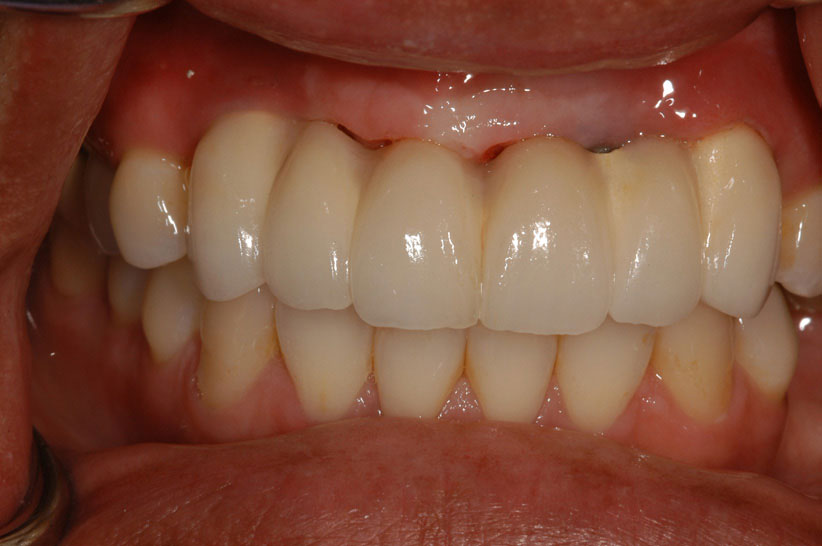

After approximately 4 months of healing, the final denture can be fabricated. This can be made of acrylic or porcelain. Both achieve great esthetic results, but porcelain is three to four times more expensive. Recent studies show that it is beneficial to splint implants together with a fixed temporary denture versus a removable transitional denture because it decreases the risk of failure.23

As stated earlier, dentures replace approximately 10% of chewing function. This causes digestive problems due to an inability to chew the food properly, also leading to malnutrition, due to eating only softer, more processed foods. Atrophy of the alveolar arches occurs due to lack of adequate pressure on the bone. This atrophy results in resorption of the tissues leading to mouth sores and tissue irritation. When the denture is allowed to irritate the mental foramen, the patient can experience pain and numbness of the lower lip. A positive solution for a denture patient is to have two to four implants inserted into the alveolar bone. The denture is then connected to the implants via snap-on attachments or a bar resulting in stabilization (Figure 21 through Figure 23). According to the 2002 McGill Consensus Statement on overdentures, mandibular two-implant overdentures are superior to conventional dentures in all clinical trials, even up to 9 years following insertion.36

Figure 22 – Maxillary bar that attaches the overdenture

Figure 22

Figure 23 – Fully edentulous patient restored with maxillary and mandibular implant supported implants

Figure 23